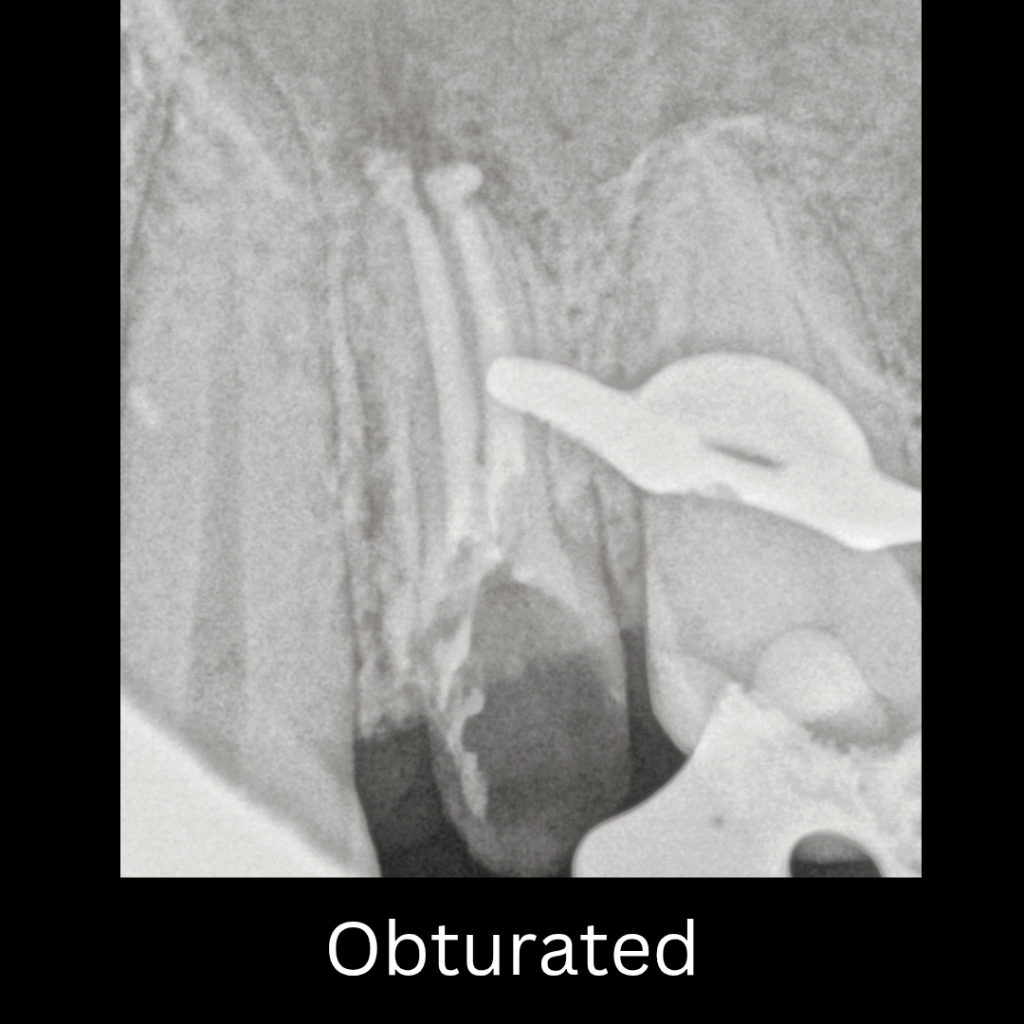

Obturation: The canal was dried, and obturation was performed using Bioceramic Sealer in conjunction with the Single-Cone Technique, ensuring a hermetic seal.

Post-Obturation Radiograph: A final radiograph was taken to verify the quality and length of the obturation.

obturation done using bioceramic sealer and single cone technqiue